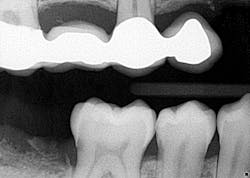

- Teeth nos. 14 and 15 both had supererupted into the 18 and 19 space (figure 2).

- Additional caries were noted on nos. 10, 11, 14, 26, 27, and 29—primarily facial/buccal caries (figures 3–8)